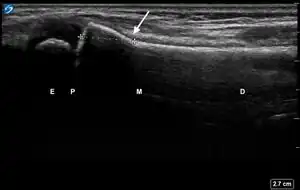

![]() Ultrasound lateral view of normal radius. E = epiphysis; P = physis; M = metaphysis; D = diaphysis. | |